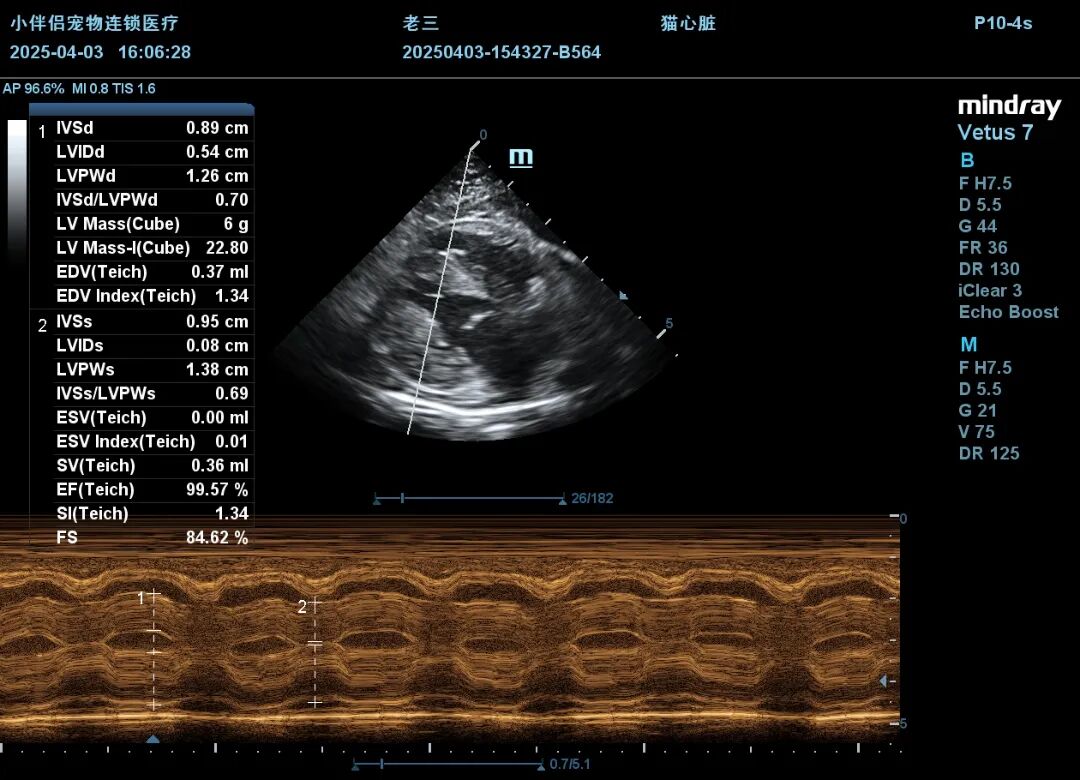

在尿闭治疗第五天,猫咪突然出现呼吸急促、咳嗽症状,因其有家族心脏病史,遂进行X光、心超、BNP、鹏佑猫肥厚型心肌病核酸检测,结果如下:

4.3心超M超.JPG

(左心室肥厚,SAM征)